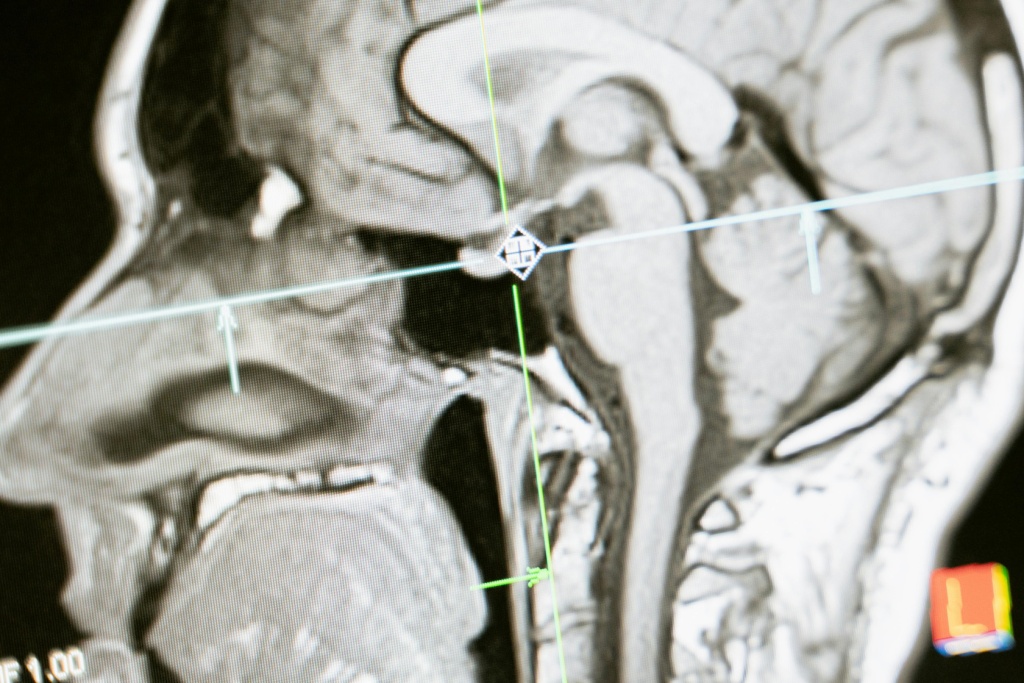

Предположим, у пациента обнаружили подозрительные изменения в тканях мозга на рентгеновских снимках. Для более точной диагностики врач назначает ему МРТ. Благодаря пониманию режимов МРТ, радиолог способен выбрать оптимальные параметры сканирования, что позволит получить высококачественные изображения мозговых структур с высоким разрешением. Это поможет точно определить характер и стадию заболевания и разработать наиболее эффективный план лечения для пациента.

В диагностике режим Т1-взвешенной МРТ широко применяется для обнаружения опухолей, кровоизлияний, инфарктов и других изменений в мягких тканях организма. Этот метод также полезен для оценки состояния мозга, позвоночника, суставов и органов грудной клетки.

Рассмотрим ситуацию, когда пациент обращается к врачу с жалобами на головные боли и головокружения. Врач назначает ему МРТ головного мозга в режиме Т1-взвешенной последовательности для выявления возможных патологий. После анализа полученных изображений врач обнаруживает опухоль в головном мозге, что позволяет начать своевременное лечение и повышает шансы на успешное исход.